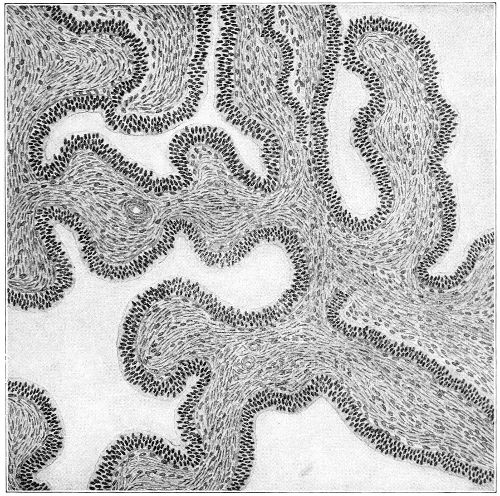

In granular vaginitis, which is the variety usually seen, the papillæ are infiltrated with small cells, and are much enlarged, so that the inflamed surface has a granular appearance.